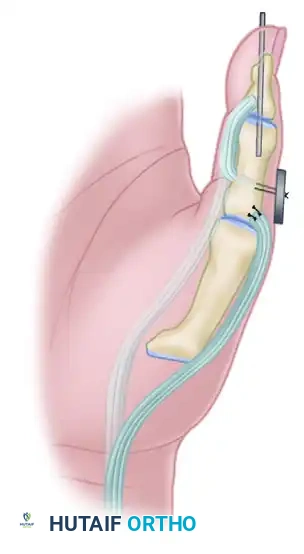

For Adults (Skeletal Maturity Achieved): Arthrodesis

- Expose the IP joint by elevating the extensor apparatus dorsally or through the existing midlateral approach.

- Denude the articular cartilage of the head of the proximal phalanx and the base of the distal phalanx down to bleeding subchondral bone using a rongeur or a small oscillating saw.

- Coapt the bony surfaces in approximately 15 degrees of flexion.

- Fix the joint securely using a retrograde crossed Kirschner wire (K-wire) technique or a headless compression screw.

For Children (Open Physes): Tenodesis

- To avoid iatrogenic injury to the open physis of the distal phalanx, an arthrodesis is contraindicated.

- Instead, perform a tenodesis of the distal FPL stump to the proximal phalanx.

- Suture the FPL stump to the periosteum or through drill holes in the proximal phalanx, securing the IP joint in 15 degrees of flexion. Alternatively, a pull-out button technique can be utilized for rigid temporary fixation while the tenodesis heals.